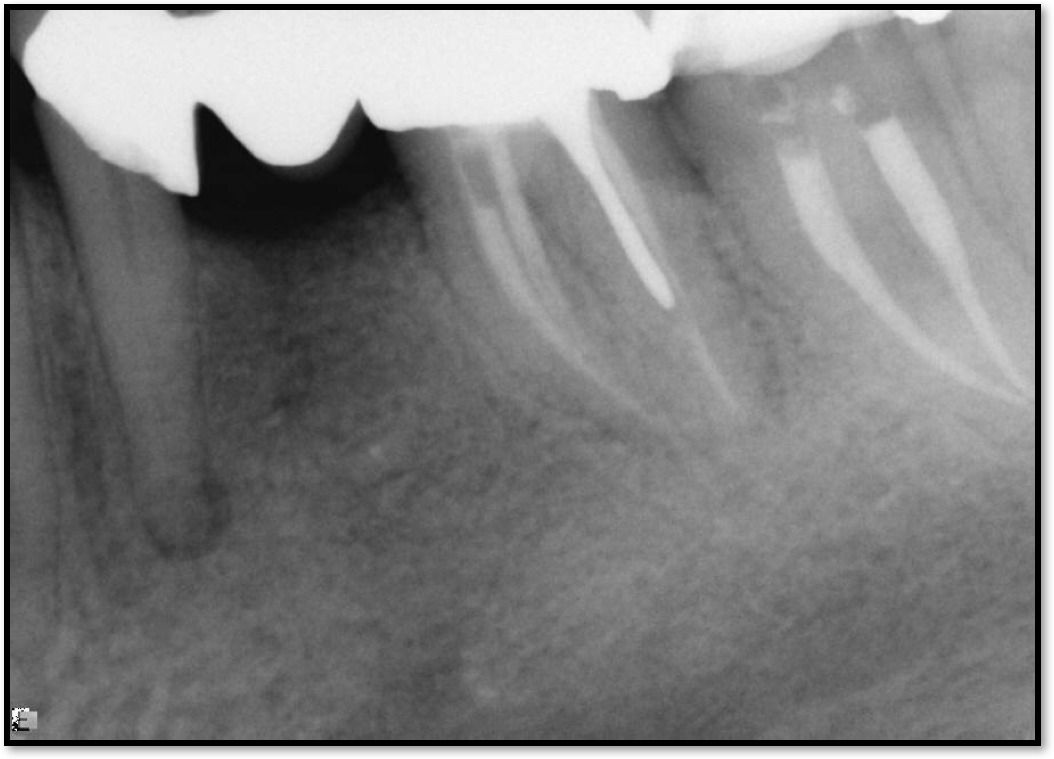

Occlusion is one of the most overlooked areas in endodontics; however, other than remaining structure, it is the most important factor.7 Patients who are heavy bruxers can cause the need for a root canal from the lateral forces. Patients who clench pose a different challenge with apical forces, yet the damage from both can be the same. Figure 7 shows a patient with bruxism. The patient had pain in response to hot and cold stimulus, and the clinicians needed a bitewing to determine which tooth was causing the pain. From the periapical (PA), it was clear that tooth No. 2 had a large problem, No. 3 had a crown, and No. 4 had a large restoration. Any of the three may have been the source of the problem.

With the bitewing shown in Figure 8, it became clear there was gross decay in tooth No. 3 that could not be seen on the PA, and there was a periodontal defect, a pulp stone, in No. 2. There was also a class V lesion revealing the bruxism, flat occlusion, multiple restorations in No. 30, a post in No. 31, and decay on No. 2 as well. The post in No. 31 was useless because when a post is placed, it must be the right length, width, and size. If the post is too short, there will be a greater fulcrum and the tooth will break. If it is too long, the clinician can break it by wedging it. If it is too short, it will not hurt the tooth, but it will not provide any valuable function. It is overall preferable to do posts in teeth having just single restorations rather than abutments for bridges because those teeth are already under greater force. If the technique is not performed correctly, iatrogenic issues may result.

Fig 7. Bruxism.

Figure 7

Fig 8. Bitewing revealed decay and other problems.

Figure 8